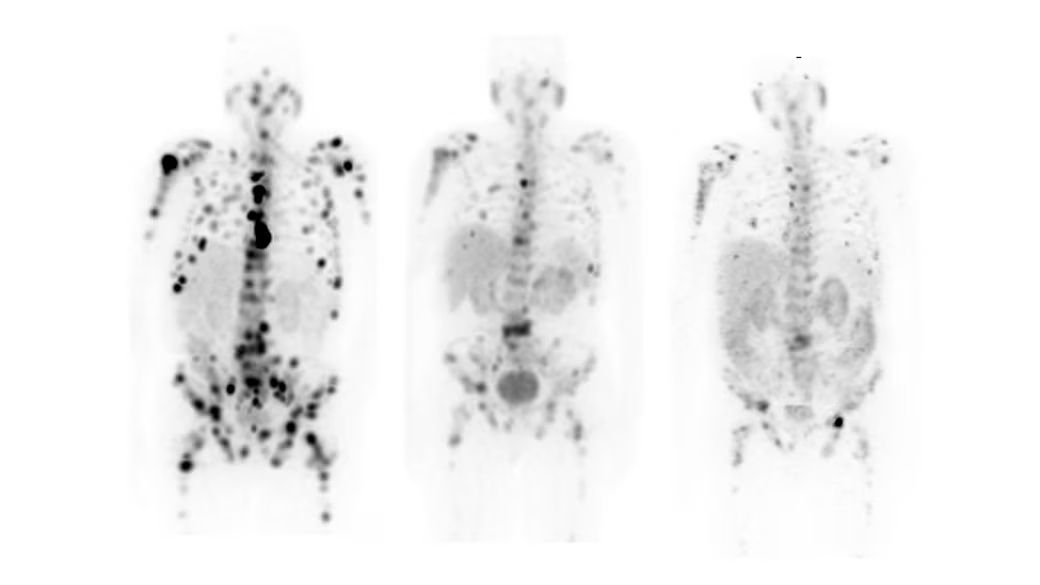

StarGuide’s high resolution, sensitivity, and contrast-to-noise ratio are the product of an innovative digital CZT detector design with optimized collimators and an advanced NM image reconstruction suite. Improved image quality performance may help physicians read images with confidence; StarGuide’s powerful, deep learning-trained Clarify DL algorithm improves image quality, with or without CT. Add to Clarify DL other advanced capabilities like CZT-optimized scatter correction and the images speak for themselves.

The potential of SPECT imaging has become exceptionally clear. With Clarify DL’s revolutionary AI technology, SPECT imaging is elevated to a new plateau. Clarify DL leverages deep learning to improve bone scan image quality performance, and improved image quality may help raise diagnostic confidence.⁶ Clarify DL is trained on thousands of bone SPECT images to reduce noise while maintaining signal contrast, for increased contrast-to-noise ratio (CNR).⁷ Clarify DL produces clear, accurate, and effortless imaging.